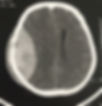

A NeurAll ITZ está em Imperatriz para prestar serviços de excelência em consultas e cirurgias neurológicas.

Atua nas áreas de Neurocirurgia geral adulto e pediátrica e cirurgia da coluna vertebral.